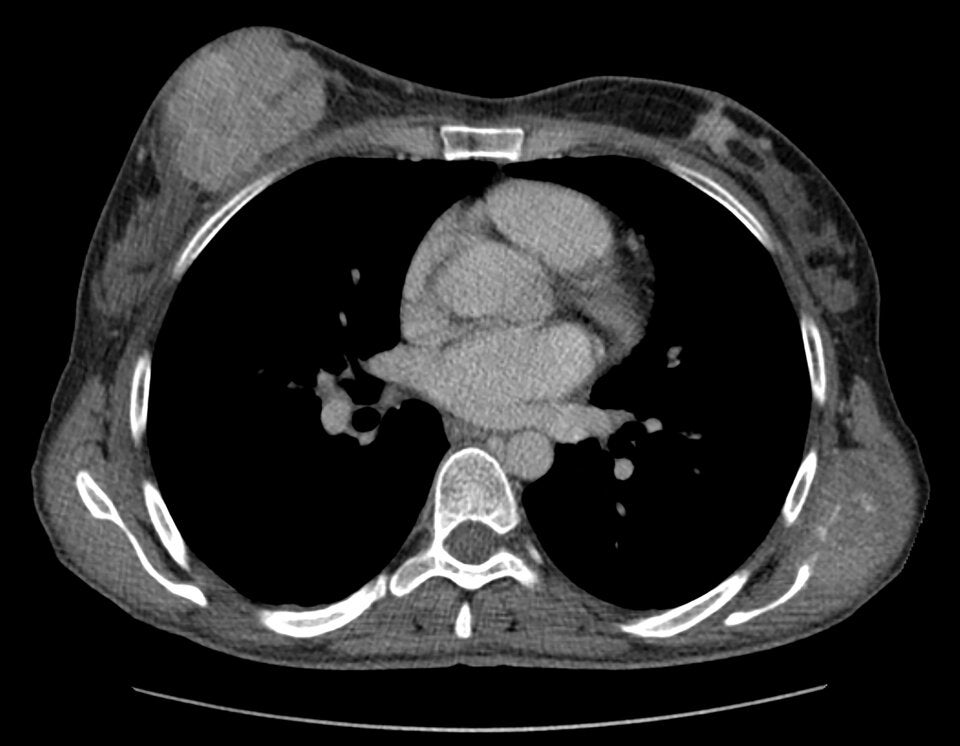

Brustkrebs trifft immer öfter junge Frauen und eine neue Studie zeigt, wie ernst die Lage wirklich ist. Viele Tumore werden spät entdeckt, Screeningprogramme setzen zu spät an und die Zahlen steigen. Warum das so ist und was junge Frauen jetzt wissen sollten.

Brustkrebs galt lange als Erkrankung, die vor allem Frauen ab 50 betrifft. Doch inzwischen zeigt sich ein anderes, beunruhigendes Bild: Immer mehr junge Frauen erhalten die Diagnose, teilweise weit vor ihrem 40. Geburtstag. Und eine aktuelle US-Studie bringt nun neue Details ans Licht, die deutlich machen: Wir müssen umdenken.

Verschiedene internationale Auswertungen zeigen schon länger, dass die Kurve bei den unter 40-Jährigen nach oben zeigt. Weltweit nahm die Zahl der Diagnosen in den vergangenen drei Jahrzehnten deutlich zu. Die globalen Daten sprechen eine klare Sprache: Die Erkrankungsrate junger Frauen ist seit den 1990ern kontinuierlich gestiegen, teilweise sogar dramatisch.

Gleichzeitig steht man vor einem strukturellen Problem: Klassische Brustkrebs-Früherkennung setzt erst ab 40 oder 45 an. Frauen darunter? Kommen normalerweise gar nicht in Screening-Programme, obwohl gerade bei ihnen die Tumore oft aggressiver wachsen und schneller streuen.

Ein Forschungsteam aus den USA hat jetzt genauer hingeschaut. Sie analysierten die Daten von sieben ambulanten Einrichtungen rund um New York. Ergebnis: knapp 1.800 Brustkrebsfälle wurden bei Frauen zwischen 18 und 49 Jahren in den letzten zehn Jahren diagnostiziert. Das heißt: jede fünfte Brustkrebsdiagnose betraf Frauen unter 50 - ein erstaunlich hoher Anteil.

• Durchschnittsalter bei Diagnose: 42,6 Jahre

• Über 80 Prozent der Tumore waren invasiv, also bereits dabei, sich über das ursprüngliche Gewebe hinaus auszubreiten

• Frauen unter 40 hatten überdurchschnittlich häufig besonders aggressive Tumorformen

Und noch etwas sticht heraus: Die Anzahl der Fälle blieb über die ganze Untersuchungszeit hinweg konstant hoch, obwohl in dieser Altersgruppe insgesamt weniger Vorsorgeuntersuchungen stattfinden. Mit anderen Worten: Diese Diagnosen sind kein Ausreißer. Sie sind ein Trend.

Radiologin Stamatia Destounis, die die Studie betreut hat, bringt es auf den Punkt: Frauen unter 40 sollten nicht automatisch als „niedriges Risiko“ eingestuft werden. Stattdessen brauche es deutlich frühere Risikoeinschätzungen - zum Beispiel für Frauen mit familiärer Belastung, bestimmten Genmutationen oder aus Gruppen mit erhöhtem Risiko.